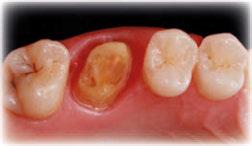

Figuras 4 y 5. Imagen intraoral y de sonrisa de la paciente en la primera visita. En ellas observamos el colapso de la mordida a nivel anterior, con una sobremordida del 100%.

Figuras 6 y 7. Al retirar las prótesis removibles observamos en el arco inferior una gran reabsorción ósea del sector posterior, con elevación del suelo de la boca y la invasión de los tejidos blandos, lo que nos hace suponer que existe una gran atrofia ósea asociada.